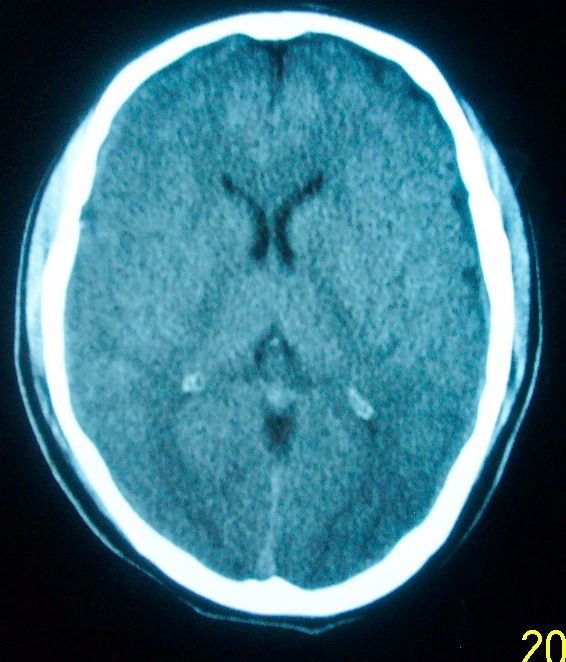

m     29    外伤1天   ct发现左额脑沟异常   请分析

我认为仅仅是左侧额叶脑回局部发育不良,脑沟与蛛网膜下腔略扩大而已没有巨脑回、硬膜下积液等情况。